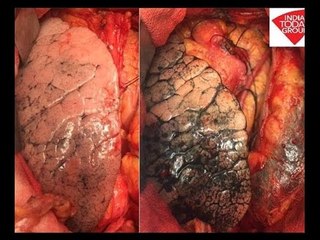

Lungs Transported From Ahmedabad To Delhi In 3 Hrs Via Air